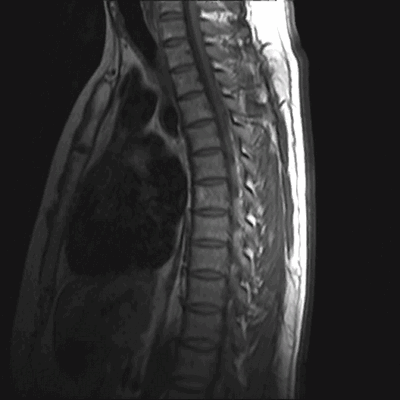

Расшифровка МРТ позвоночника

Гемангиомы на магнитно-резонансной томографии грудного отдела позвоночника (сагиттальная проекция, Т2 взвешенная последовательность)

МРТ позвоночника - высокоинформативный метод диагностики, использующий для построения детальных изображений структур области интереса свойства магнитного поля, радиоволны и компьютерную обработку. По показаниям исследование выполняют с контрастным усилением: в вену вводят препарат, содержащий хелаты гадолиния.

Как выглядит фото-снимок МРТ позвоночника

МРТ грудного отдела позвоночника (сагиттальная проекция, Т1 ВИ)

Магнитно-резонансные томограммы отображают внутренние структуры зоны интереса в трех плоскостях. Каждый снимок представляет собой один срез, на распечатанном фото МРТ их несколько.

В норме позвонки гладкие, повреждения отсутствуют. Фиброзно-хрящевые диски, выполняющие роль амортизаторов, не выпячиваются, имеют стандартную высоту, без признаков дегенерации. Спинной мозг выглядит на фото как белый шнур без видимых перекосов и других изменений.

При патологических процессах снимки могут демонстрировать:

- искривления позвоночного столба - сколиоз, лордоз, кифоз;

- злокачественные и доброкачественные новообразования (для верификации опухоли выполняют биопсию);

- метастазирование в позвонки;

- кистозные полости;

- смещения и переломы позвонков, растяжения связок, отдаленные последствия травмы;

- протрузии, дегенеративные изменения (спондилодисцит, остеохондроз и др.), грыжи, признаки вовлечения в патологический процесс спинномозговых корешков;

- поражение замыкательных пластинок;

- миелоишемию;

- участки сужения позвоночного канала, компрессию или повреждение спинного мозга и пр.